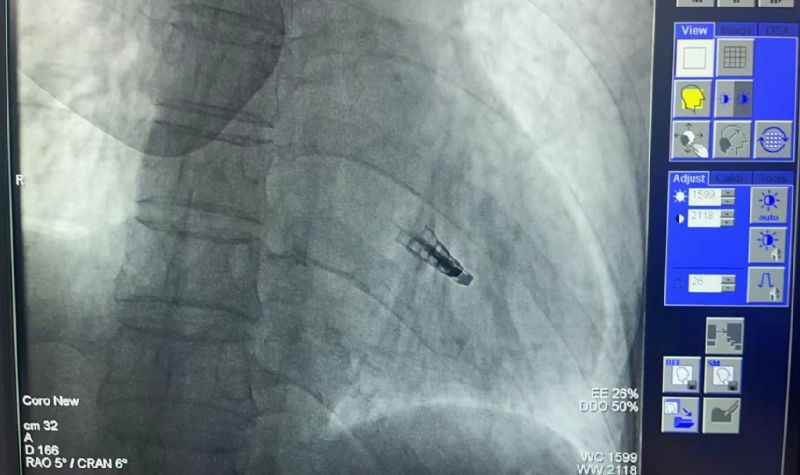

2025年5月9日,延安大學(xué)咸陽(yáng)醫(yī)院常務(wù)副院長(zhǎng)兼心血管病院院長(zhǎng)吳棟梁介入團(tuán)隊(duì)成功為一名73歲“二尖瓣大量返流”患者實(shí)施咸陽(yáng)市首例《經(jīng)導(dǎo)管二尖瓣緣對(duì)緣修復(fù)術(shù)(TEER)》。

創(chuàng)傷極小:不開(kāi)胸的“心臟修補(bǔ)術(shù)”。僅通過(guò)股靜脈穿刺,經(jīng)導(dǎo)管送入夾合器精準(zhǔn)修復(fù)二尖瓣,避免傳統(tǒng)開(kāi)胸、體外循環(huán)等高風(fēng)險(xiǎn)操作。

高效精準(zhǔn):手術(shù)耗時(shí)僅1-2小時(shí),術(shù)后患者即刻返流顯著減少,血流動(dòng)力學(xué)明顯改善。

術(shù)前吳棟梁院長(zhǎng)、劉雄濤院長(zhǎng)、張樹(shù)遠(yuǎn)責(zé)任總醫(yī)師再次深入的評(píng)估患者整體病情及手術(shù)指征,于2025年5月9日下午成功為患者實(shí)施了TEER技術(shù),解除了其病痛,術(shù)后第一天患者即表示“呼吸順暢了,整個(gè)人都輕松了”。